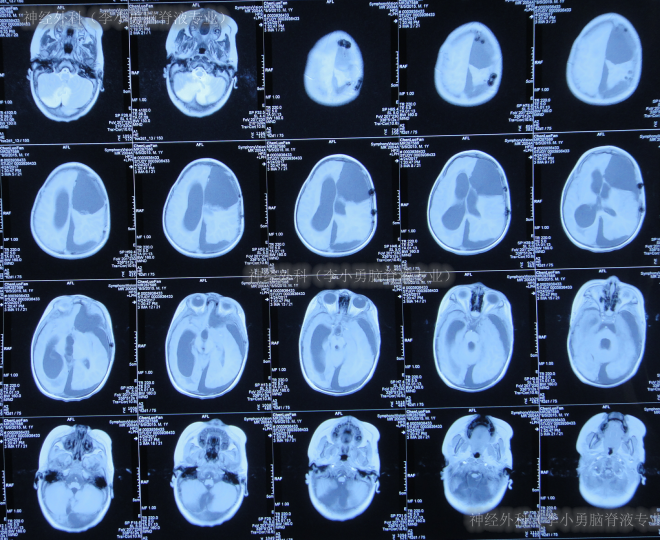

入院时头颅CT示癫痫术后,左侧额顶骨术后改变,左侧侧脑室引流术后状态,幕上脑室系统扩,多处硬膜下积液、部分见积气(图-16)。

图-16:2017年7月20日头颅CT